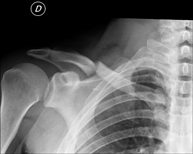

- Limb X-ray

This technique uses X-ray imaging to examine the limbs, especially the bones. Indicated for: trauma, joint infections.

- Pelvis X-ray

This procedure uses X-ray imaging to examine the pelvis, especially the pelvic bones.